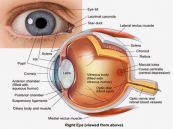

Tăng nhãn áp dùng để chỉ một nhóm bệnh về mắt gây thiệt hại cho các đầu dây thần kinh thị giác và mất dần các tế bào hạch võng mạc cũng như sợi trục thần kinh, dẫn đến tình trạng suy yếu thị giác. Cùng eLib.VN tìm hiểu bài viết dưới đây để hiểu rõ hơn về bệnh lý này nhé!

Bệnh tăng nhãn áp góc đóng nguyên phát là một loại bệnh ngăn chặn hệ thống thoát nước mắt qua lưới sợi mô liên kết, bao gồm bệnh tăng nhãn áp góc đóng cấp tính và tăng nhãn áp góc đóng mạn tính. Cùng eLib.VN tìm hiểu bài viết dưới đây để hiểu rõ hơn về bệnh lý này nhé!

Tăng nhãn áp góc đóng cấp tính là một tình trạng vô cùng nghiêm trọng khi áp lực bên trong mắt (áp lực nội nhãn, nhãn áp hay IOP) tăng đột ngột, xảy ra khi dòng thủy dịch bị chặn lại không chảy ra ngoài được. Trường hợp này cần được điều trị khẩn cấp, nếu không có thể dẫn đến mất thị lực vĩnh viễn. Để biết rõ hơn về bệnh lý này, mời các bạn tham khảo bài viết dưới đây.

Tăng nhãn áp bẩm sinh nguyên phát là một loại bệnh tăng nhãn áp, khi áp lực dịch trong mắt cao và gây tổn thương đến thần kinh thị giác. Bệnh này thường được chẩn đoán khi sinh hoặc ngay sau đó và hầu hết các trường hợp đều được chẩn đoán trong năm đầu tiên của trẻ. Để biết rõ hơn về bệnh lý này, mời các bạn tham khảo bài viết dưới đây.

Tăng nhãn áp còn có các tên gọi khác như: bệnh thiên đầu thống, cườm nước và glocom. Đây là một bệnh về mắt thường gặp. Do tăng áp lực nhãn cầu nên người bệnh nhìn mờ và đau đầu. Nếu áp lực nhãn cầu cao kéo dài sẽ chèn ép làm tổn thương thần kinh thị giác phía sau và có thể gây mù lòa nếu không được chữa trị kịp thời. Có nhiều nguyên nhân gây bệnh, do đó sẽ có các phương pháp điều trị khác nhau tùy theo bệnh sinh. Cùng eLib.VN tìm hiểu bài viết dưới đây để hiểu rõ hơn về bệnh lý này nhé!